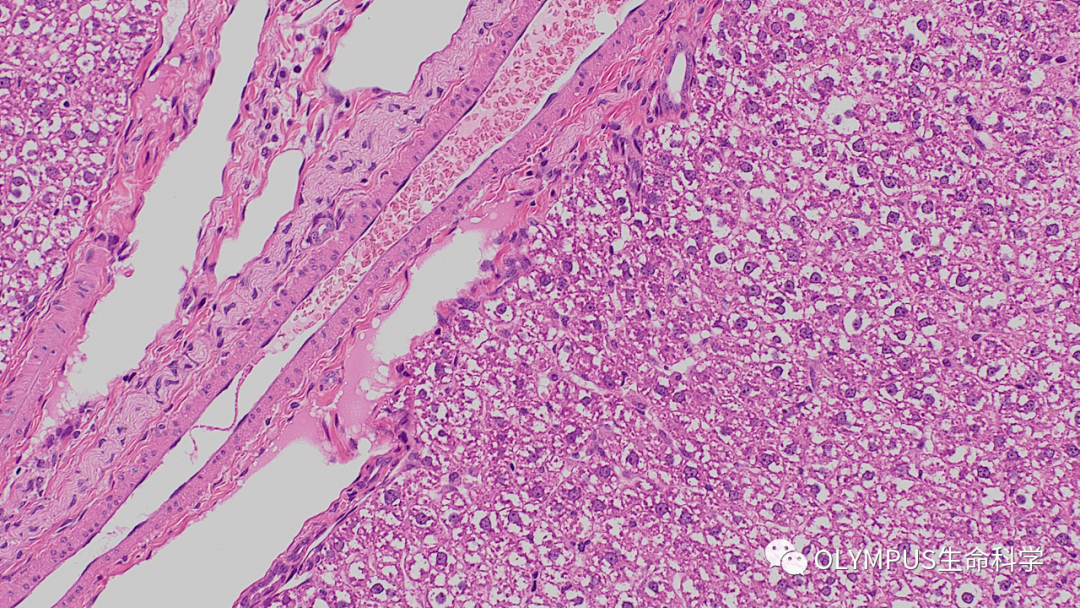

小鼠乳腺

物鏡:UPLXAPO20X

數(shù)據(jù)出處:中國科學(xué)院分子細(xì)胞科學(xué)卓越創(chuàng)新中心 曾藝組 劉春業(yè)